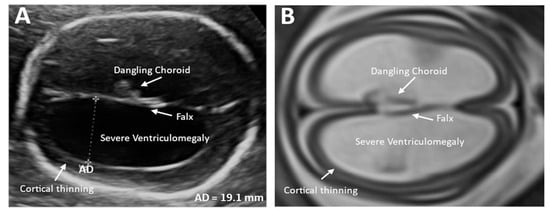

2.1. Key Findings of the Width of the Lateral Ventricles of the Fetal Brain

2.2. Ultrasound Neuroscan for Fetal VM

2.3. MRI in Fetal VM Diagnosis